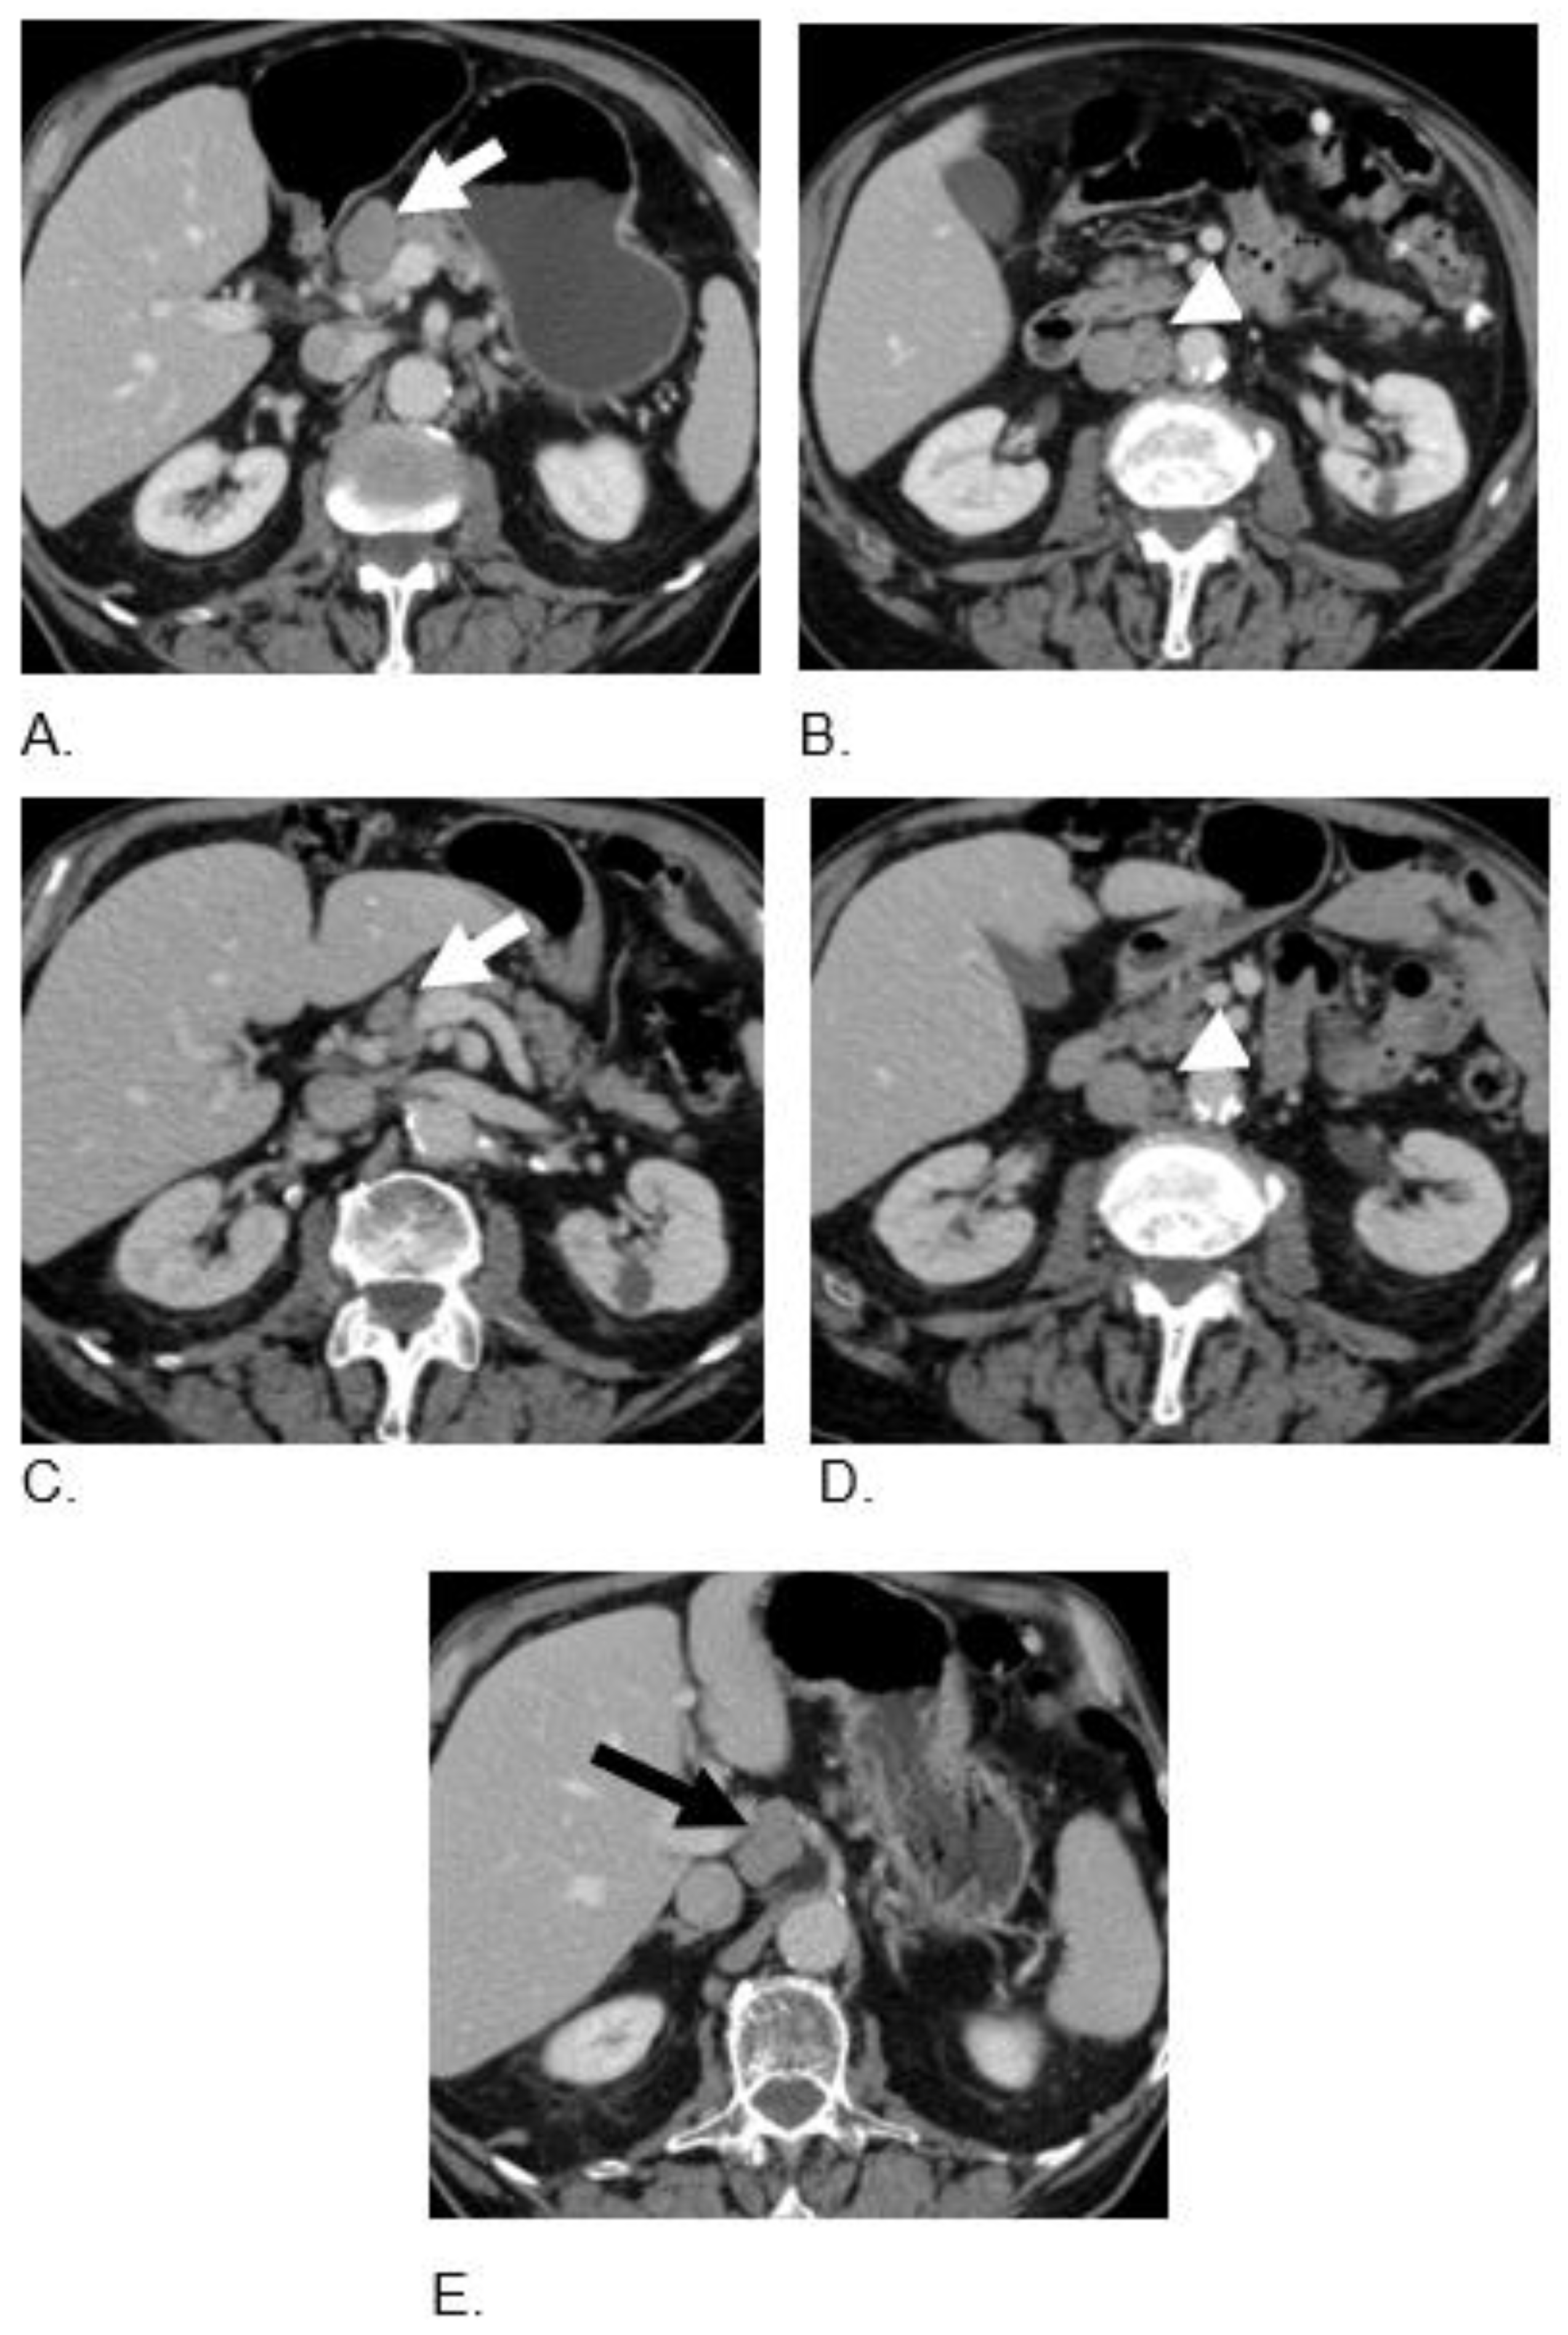

| Colon MiNEN | Mixed neuroendocrine-non-neuroendocrine neoplasm (MiNEN). | 67 | M | Carboplatin and Etoposide | Nivolumab 3 mg/kg i.v and Ipilimumab 1 mg/kg i.v. every 3 weeks for 4 cycles plus TQ-BSO (1 teaspoon oil formula daily) | Nivolumab 240 mg i.v. every 2 weeks plus BSO (TQ) tablets 1500 mg daily | Alive with CR and PFS of 10 mos |

| Colon MiNEN | Mixed neuroendocrine-non-neuroendocrine neoplasm (MiNEN). 70% small cell and 30% adenocarcinoma | 85 | M | Adjuvant mFOLFOX | Nivolumab 3 mg/kg i.v and Ipilimumab 1 mg/kg i.v. every 3 weeks for 3 cycles plus TQ-BSO (3 tablets 500 mg daily) | BSO (TQ) tablets 1500 mg daily | Alive with PR and PFS of 12 month |